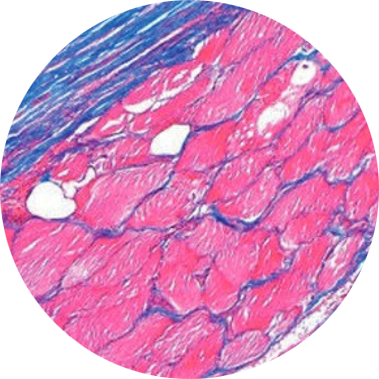

Colorações Específicas

A pesquisa de agentes infecciosos como, por exemplo, bactérias, fungos e bacilos álcool- ácido- resistentes, pode ser realizada por meio de colorações histoquímica adicionais, além da hematoxilina e eosina efetuada de rotina. O Lapac conta com um leque de colorações histoquímicas incluindo PAS (Mucina, glicogênio e fungos), Alcian-Blue (Mucina), Fite- Faraco (BAAR), Grocott-Gomori (Fungos), Vermelho-Congo (Amilóide), Giemsa (H.Pylori), etc.

Essas técnicas são realizadas nos mesmo blocos de parafinas utilizados no exame histopatológico.